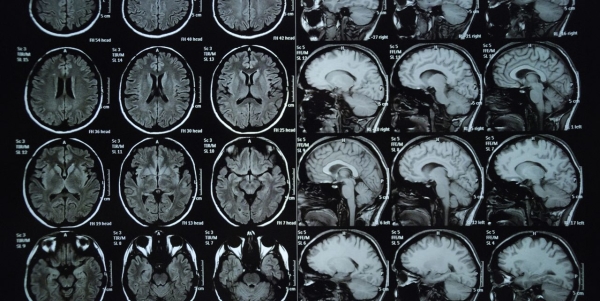

这些观念对人们解读脑科学的方式,产生了惊人的影响。随着核磁共振成像技术的出现,神经科学家一直致力于寻找男女大脑的区别。这一方向的研究备受关注,因为人们很容易将有关大脑的任何发现与行为上的性别差异联系起来。

当适当地控制大脑的总体积时,男女间各个大脑区域的差异都不超过1%。即使是微小的差异,也不会同时存在于不同地理或种族的人群中。不过,“性别二态性”这个论点不会消失。它就像一个“僵尸”概念,最近的一次兴起是利用人工智能来预测大脑扫描图像来自男性还是女性。

这一技术的精确度可以达到80%到90%,但正如上文所提到的,当你恰当地控制人脑的大小时,精确度就会下降到60%(这并不比抛硬币的概率高多少)。这种算法在不同人群中也不具备普适性。这种不一致性表明,没有任何一种普适性的特征,可以用于区分男性和女性的大脑。